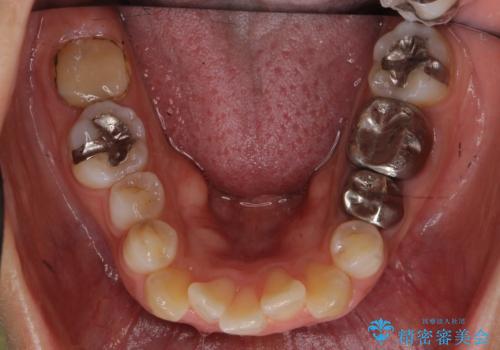

- 歯並びを主訴に来院。

左上2番は以前抜歯したとのこと。

奥歯を後ろに下げて、前歯を並べています。

マウスピースと矯正用のミニスクリューを使用して治療しています。

銀歯も白くということでしたので虫歯治療も一緒に行っています。

左上7の根の治療や左下56銀歯の治療なども行いました。

右下7は根管治療をおすすめしましたが、患者様のご希望により抜歯となり、そのスペースを利用して下の前歯をならべています。